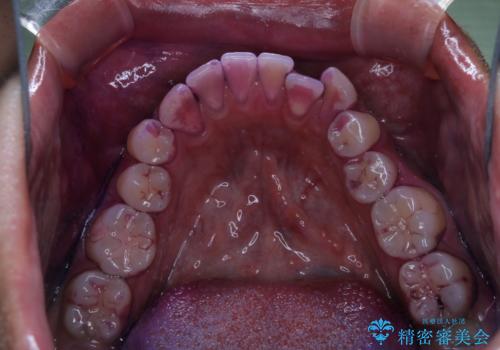

- 10年ぶりの歯科とのことで、全体の検診希望で来院されました。レントゲン撮影、歯周ポケット検査、ブラッシング指導、クリーニングを行いました。

今回はお口全体にプラーク(細菌の塊)、歯石、着色(ステイン)が付着していたため、検査後、歯科衛生士による専門的自費のPMTC(クリーニング)60分コースを行いました。

まずは、お口全体の染め出しをし、どこに汚れや磨き残しが多くついているかを明確にしました。その後、普段の歯磨きの仕方の確認や、ブラッシング指導をしました。

10年ぶりの歯科医院へ来院とのことで全体的に汚れ(バイオフィルムや着色)が多く付着してたため、自費クリーニングPMTC60分コース10000+TAXを行いました。

バイオフィルムやステインを取り除くと、ご自身本来の歯の色となります。